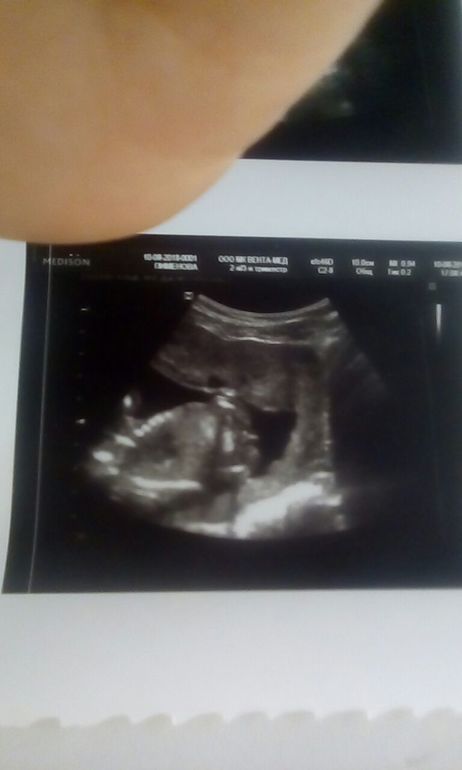

УЗИ, КТГ, доплерПрошли мы 2 скрининг,все хорошо с малышом.Так подрос,такой любимый и ,самое главное ,здоровый))) ииии.... сказали нам,что 100%девочка.Я показала предыдущее фото с двух узи из разных мест,где нам показали мальчика.Разница между узи 10 дней.Меня спросили:а фото точно твое?Говорю мое,видела все в экран.На что мне сказали,что пол узнаю после родов,но сегодня-девочка))))Так не интересно.....

узи 16 авг-девочка

Я не выдержала.Пошла сегодня на определение пола-девочка без сомнений.Мне кажется у меня муж не так расстроился как я.Хотя я вначале очень боялась мальчика и не знала,что с ним делать.Долгожданный и запланированный ребенок,мы с мужем говорили о том,что без разницы какой пол,что просто хотим еще малыша.А на деле вон какие эмоции прут,а я ничего с собой не могу поделать.Еще даже не разобралась,нужно время,чтоб принять.Одно поняла я точно-раньше 20 недель нечего спрашивать пол ребенка. А на вашем фото все-таки мальчик-стручок длинненький,а у нас,видимо,были припухшие половые губки.Хотя сегодня в том же центре и на том же экране совсем не та точность изображения